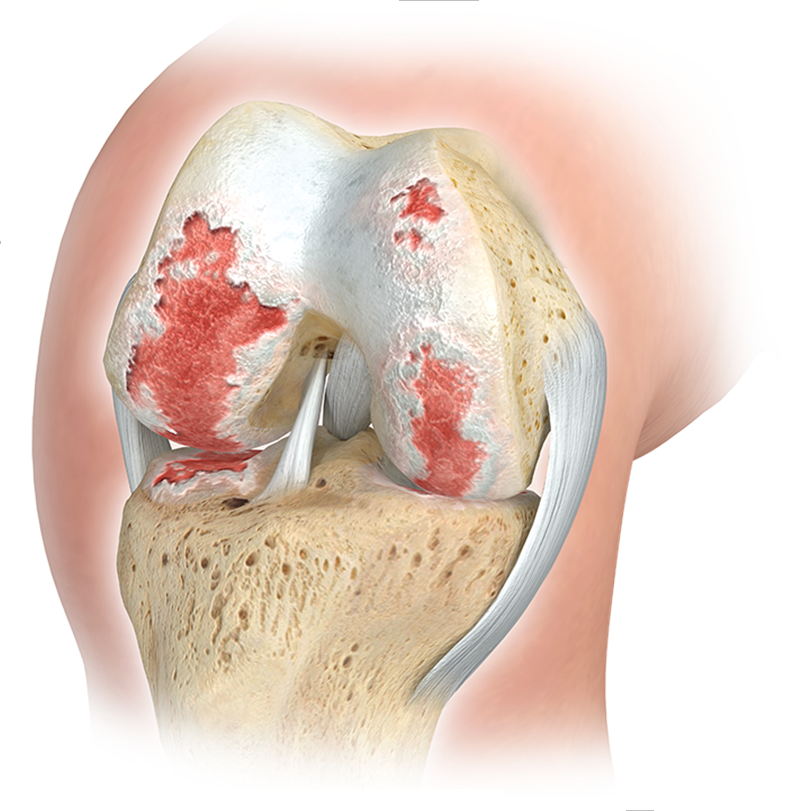

Knee osteoarthritis

Due to the high stresses to which the knee joints are subjected, wear and tear is very common over the course of a lifetime, leading to significant discomfort and limitations in quality of life. Early sports injuries, misalignments, or being overweight significantly contribute to this development.

A total knee replacement, or TKR for short, is a surgical procedure in which the worn surfaces of the knee joint are replaced with high-quality implants made of metal and plastic. This joint replacement mimics the natural function of the knee and restores smooth and pain-free movement. Such a procedure is generally recommended when the articular cartilage is so severely damaged by osteoarthritis (gonarthrosis) that the patient suffers from persistent pain, restricted movement, and a loss of quality of life.

The artificial knee joint replaces the cartilage surface destroyed by osteoarthritis. The underlying bone of the femur and tibia remains intact. Some compare a modern artificial knee joint to a

crown on a tooth; the precise term is

bicondylar resurfacing. Between the new surfaces of the femur and tibia is an inlay made of a specially hardened white plastic, visible in X-rays as a gap between the metal components.